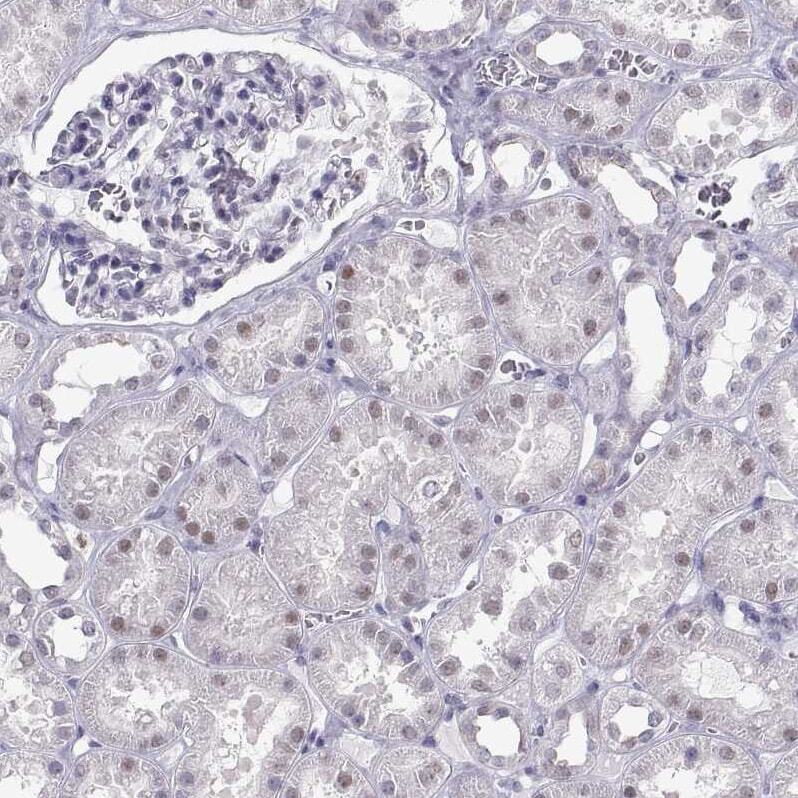

- Submitted by

- Invitrogen Antibodies (provider)

- Main image

- Experimental details

- Immunohistochemical analysis of C16orf59 in human kidney using C16orf59 Polyclonal Antibody (Product # PA5-84253) shows weak nuclear positivity in cells in tubules.